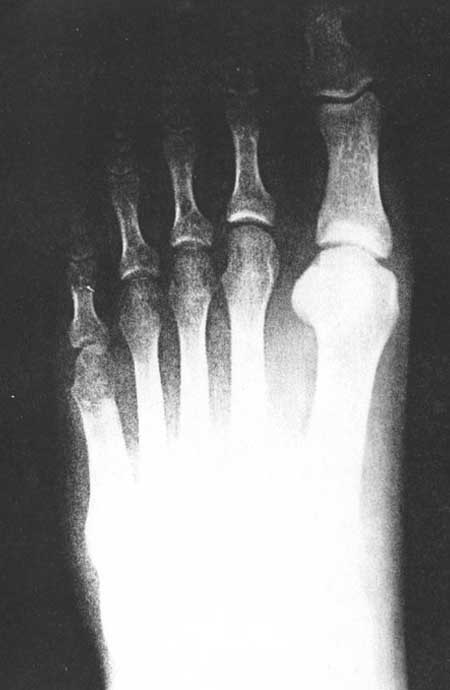

Fig 3C (pre-operative)

|

Fig 3C (post-operative)